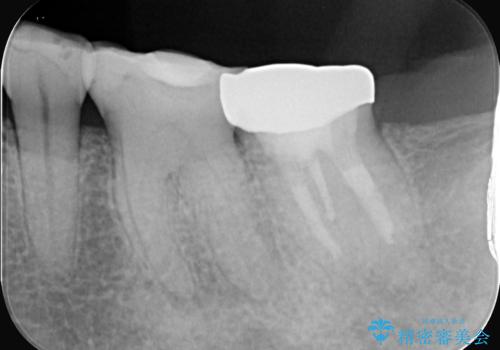

- 2日前から歯の痛みが続くという主訴でご来院されました。診察の結果、**不可逆性歯髄炎(歯の神経の重度の炎症)**と診断。レントゲンでは、歯髄腔が狭くなり、根管が石灰化している難症例であることが確認されました。患者様の大切な歯を残すため、歯科用顕微鏡を用いた精密根管治療を行うことで、狭く、見えにくい根管を正確に探し出し、治療を完了させる計画を立案しました。

今回の治療は、特に難易度の高い石灰化した根管が対象でした。まず、治療中の細菌感染を防ぐためにラバーダムを使用。次に、歯科用顕微鏡で治療部位を何十倍にも拡大しながら、狭窄した根管の入り口を探し、慎重に拡大・清掃を行いました。顕微鏡を用いることで、肉眼では不可能だった根管内部の細かい構造を確認しながら、感染源を徹底的に除去することができました。これにより、難症例の奥歯でも再発リスクを抑えた適切な処置を行うことができ、治療後に痛みは解消。大切な歯を長期間にわたり保存することができました。